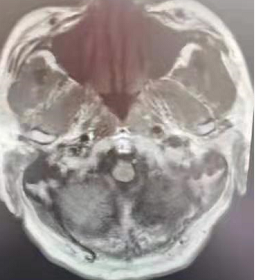

在溶栓治疗1个小时后,患者口齿逐渐清楚,右侧肢体肌力逐渐恢复;3个小时后,及时行MRI-头部扫描。扫描结果显示:左侧脑室体部旁、左侧基底节区急性缺血缺氧脑损伤,左侧大脑中动脉M3段起始处局部变窄。扫描结果坚定了医护人员的信心。在溶栓治疗24小时后,再次复查颅脑CT,并将结果与溶栓3+小时颅脑MRI片进行了比较,显示:颅脑左侧基底节豆状核提示脑梗塞。针对对比结果,继续跟进后期治疗方案。经过系列治疗,患者右侧肢体肌力已基本恢复,约Ⅴ-级,无言语障碍,无头晕、头痛等不适,转入内一科普通病房观察治疗。